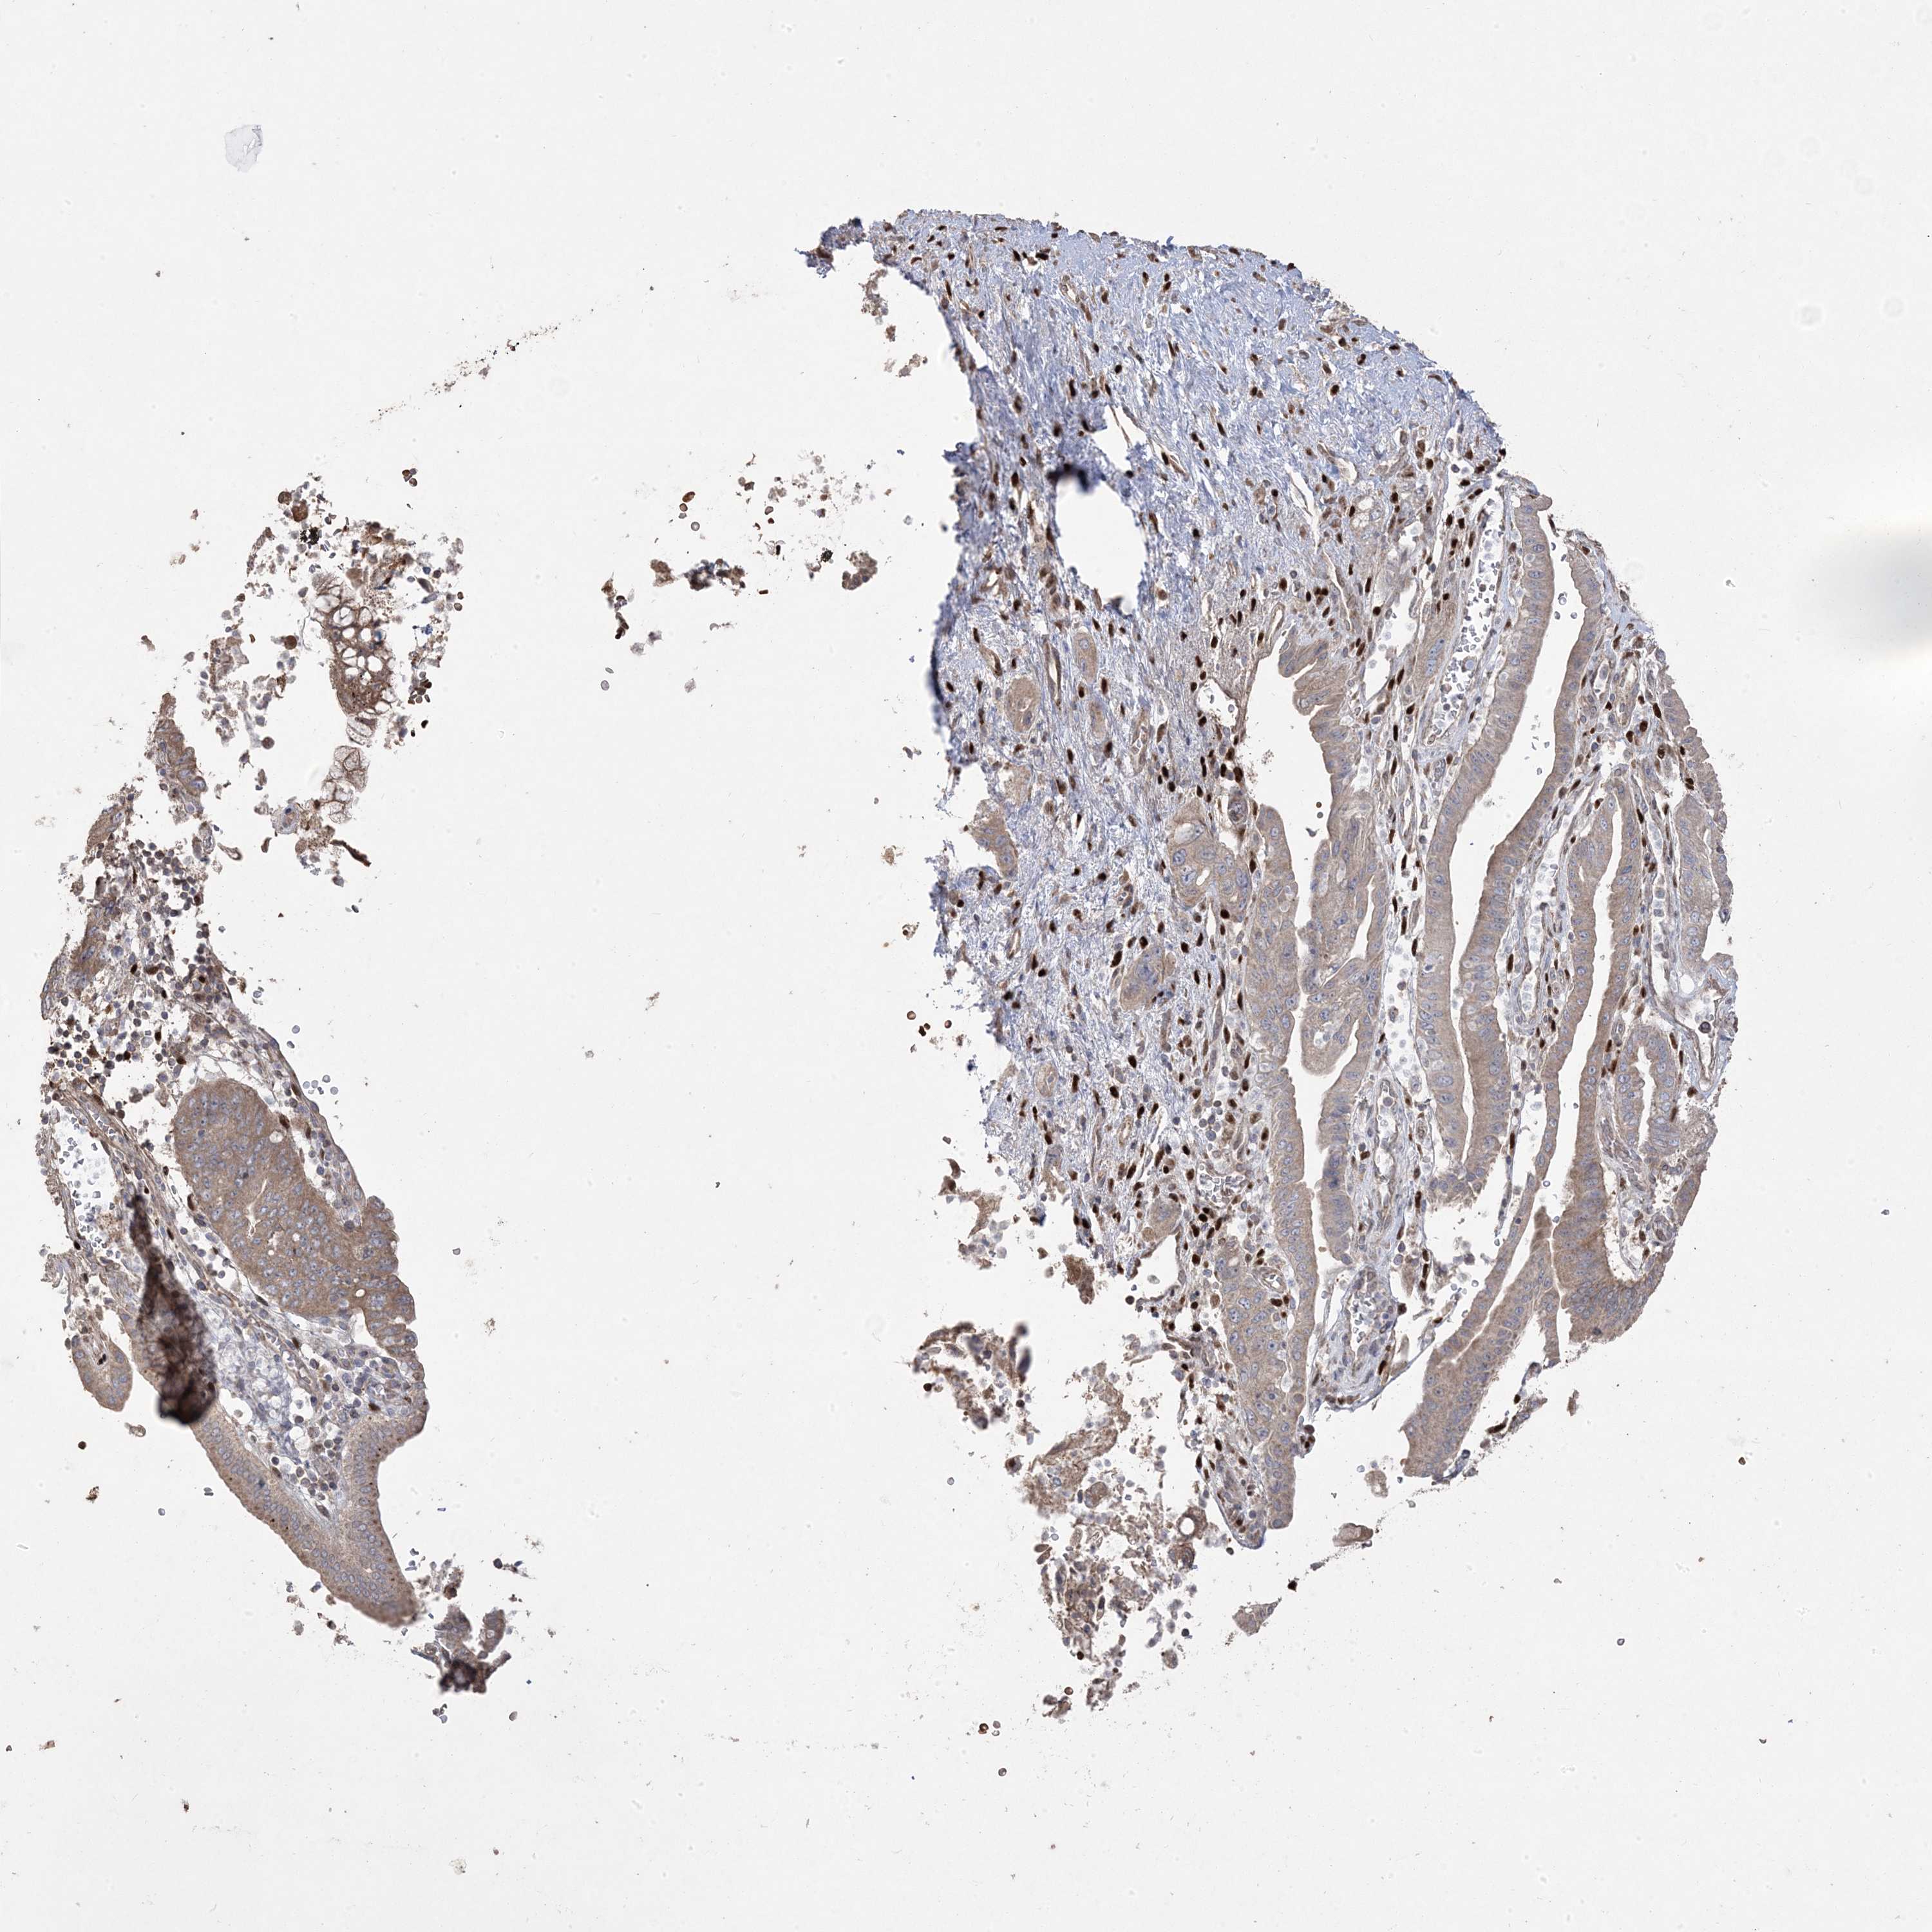

PANCREATIC CANCER - Protein expressioni

A mouse-over function shows sample information and annotation data. Click on an image to view it in a full screen mode. Samples can be filtered based on level of antibody staining by selecting one or several of the following categories: high, medium, low and not detected. The assay and annotation is described here.

Note that samples used for immunohistochemistry by the Human Protein Atlas do not correspond to samples in the TCGA dataset.

Antibody stainingi

Antibody staining in the annotated cell types in the current human tissue is reported as not detected, low, medium, or high, based on conventional immunohistochemistry profiling in selected tissues. This score is based on the combination of the staining intensity and fraction of stained cells.

Each image is clickable and will lead to virtual microscopy that enables deeper exploration of all samples and also displays staining intensity scores, fraction scores and subcellular localization as well as patient and tissue information for each sample.

Antibody HPA030123

Staining

High

Medium

Low

Not detected

Intensity

Strong

Moderate

Weak

Negative

Quantity

>75%

75%-25%

<25%

None

Location

Nuclear

Cytoplasmic/membranous

Cytoplasmic/membranous,nuclear

Adenocarcinoma, NOS